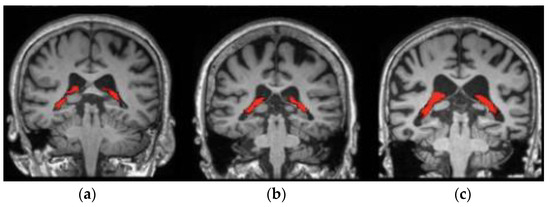

The proposed fuzzy-based superpixel-clustering algorithm and the MGTO-CapsNet model performance was tested on the ADNI, real time, and AIBL datasets. The ADNI dataset comprises 1662 sMRI images; here, the individuals are categorized into three types, including normal control (NC), AD, and mild cognitive impairment (MCI) [35]. The goal of ADNI is to create biochemical, genetic, imaging, and clinical biomarkers for the early identification and monitoring of AD. The historic public–private cooperation, which was established more than ten years ago, has significantly advanced AD research by facilitating the exchange of data amongst researchers worldwide (https://adni.loni.usc.edu/data-samples/) accessed on 14 November 2023. Furthermore, the AIBL dataset (https://aibl.csiro.au) accessed on 21 November 2023 consists of 496 sMRI images, and the individuals are categorized into three types, including 17 progressive MCI (pMCI), 93 stable MCI (sMCI), and 307 NC [36] subjects. Additionally, the real-time dataset was acquired from Rajiv Gandhi Government General Hospital (Chennai), and it comprises 200 sMRI images belonging to three classes (NC, AD, and MCI). The acquired sample sMRI images from the ADNI dataset (a), including the real-time dataset (b), and AIBL dataset (c) are visually presented in Figure 2.

Figure 2. Acquired sample sMRI images: (a) ADNI dataset, (b) real-time dataset, and (c) AIBL dataset.